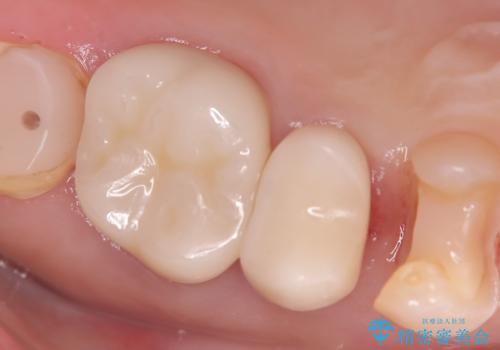

「右上4番目と5番目の間にフロスを通すといつも出血し、たまに臭いもする」という主訴で来院されました。

右上4番に歯冠色インレーが入っており、遠心側室エリアのマージン不適を認め、そこに汚れが溜まりやすい状態となっていました。